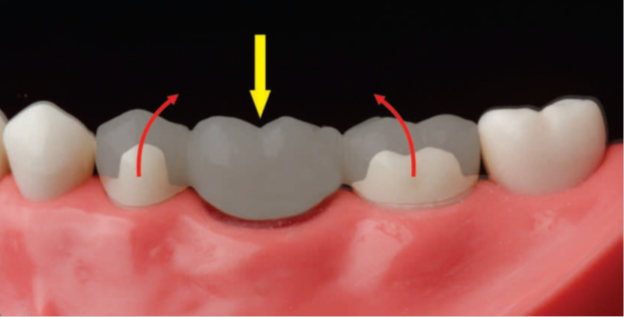

PRINCIPLES OF TOOTH PREPARATION: PART-4, New approach to expedite the delivery of the final crowns,The Tooth Preparation補綴修復治療の成功を目指した支台歯形成岩田淳 【著】2023年10月10日 A4判 312頁 24,200円(税込)医歯薬出版折り目等も特についてないので新品同様かと思います(裁断もしておりません)

New approach to expedite the delivery of the final crowns,The Tooth Preparation補綴修復治療の成功を目指した支台歯形成岩田淳 【著】2023年10月10日 A4判 312頁 24,200円(税込)医歯薬出版折り目等も特についてないので新品同様かと思います(裁断もしておりません)